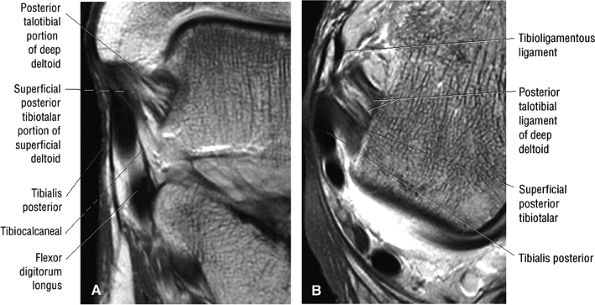

fascicle inserts onto the superior border of the calcaneona vicular ligament. The deep part of the deltoid, which is rectangular, consists of a small anterior component (the anterior tibiotalar ligament) and a strong posterior component (the posterior tibiotalar ligament) (Fig. 5.64). The posterior tibiotalar ligament represents the strongest part of the entire medial ligament complex. The deep portion of the deltoid ligament, covered by synovium, is intra-articular.

![]() |

|

FIGURE 5.58 ● transverse section through the midcalf shows the anterior and lateral compartments and their contents.